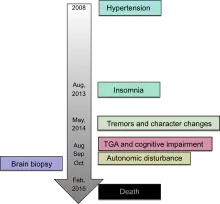

The disease has four stages:[6]

- Characterized by worsening insomnia, resulting in panic attacks, paranoia, and phobias. This stage lasts for about four months.

- Hallucinations and panic attacks become noticeable, continuing for about five months.

- Complete inability to sleep is followed by rapid loss of weight. This lasts for about three months.

- Dementia, during which the person becomes unresponsive or mute over the course of six months, is the final stage of the disease, after which death follows.

Clinically, FFI manifests with a disordered sleep-wake cycle, dysautonomia, motor disturbances, and neuropsychiatric disorders.

Other symptoms include profuse sweating, miosis (pinpoint pupils), sudden entrance into menopause or impotence, neck stiffness, and elevation of blood pressure and heart rate. The sporadic form of the disease often presents with double vision. Constipation is common as well. As the disease progresses, the person becomes stuck in a state of pre-sleep limbo, or hypnagogia, which is the state just before sleep in healthy individuals. During these stages, people commonly and repeatedly move their limbs as if they’re dreaming.[7]

The age of onset is variable, ranging from 13 to 60 years, with an average of 50.[8] The disease can be detected prior to onset by genetic testing.[9] Death usually occurs between 6–36 months from onset. The presentation of the disease varies considerably from person to person, even among people within the same family; in the sporadic form, for example, sleep problems are not commonly reported and early symptoms are ataxia, cognitive impairment, and double vision.[10]